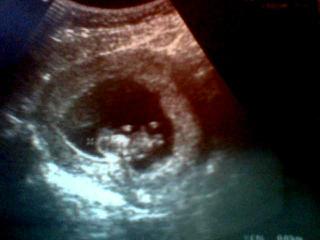

Ahojte, tak my sme sa práve vrátili zo sona, všetko v poriadku zatiaľ, bábätko sa schovávalo, vykúkalo, nakoniec zamávalo ručičkami a schovalo sa úplne 😀 až mi slzy vyskočili... nádhera!!! ešte že sa nám ju podarilo rýchlo cvaknúť 😀 (asi to bude slečna, ked bola taká hanblivá 😀 ) na fotke je otočená tváričkou a telíčkom smerom ku vám, pre prípad, že by ste to nevedeli rozlúštiť 😀 😀 😀